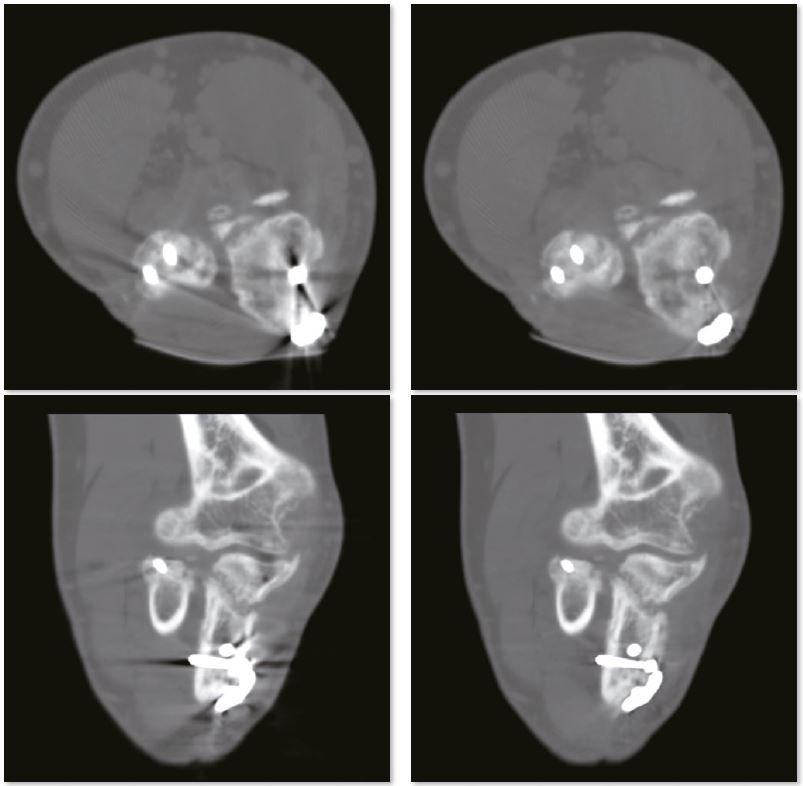

Післяопераційний гомілковостопний суглоб

Зображення SEMAR чітко демонструють перелом малогомілкової кістки. Без SEMAR перелом прихований артефактами, які заважають діагностиці. Крім того, точні положення пристроїв внутрішньої фіксації можна чітко оцінити без артефактів на зображеннях SEMAR.

Звичайне зображення гомілковостопного суглобу

Зображення гомілкостопного суглобу з SEMAR

Звичайне зображення

Зображення з SEMAR